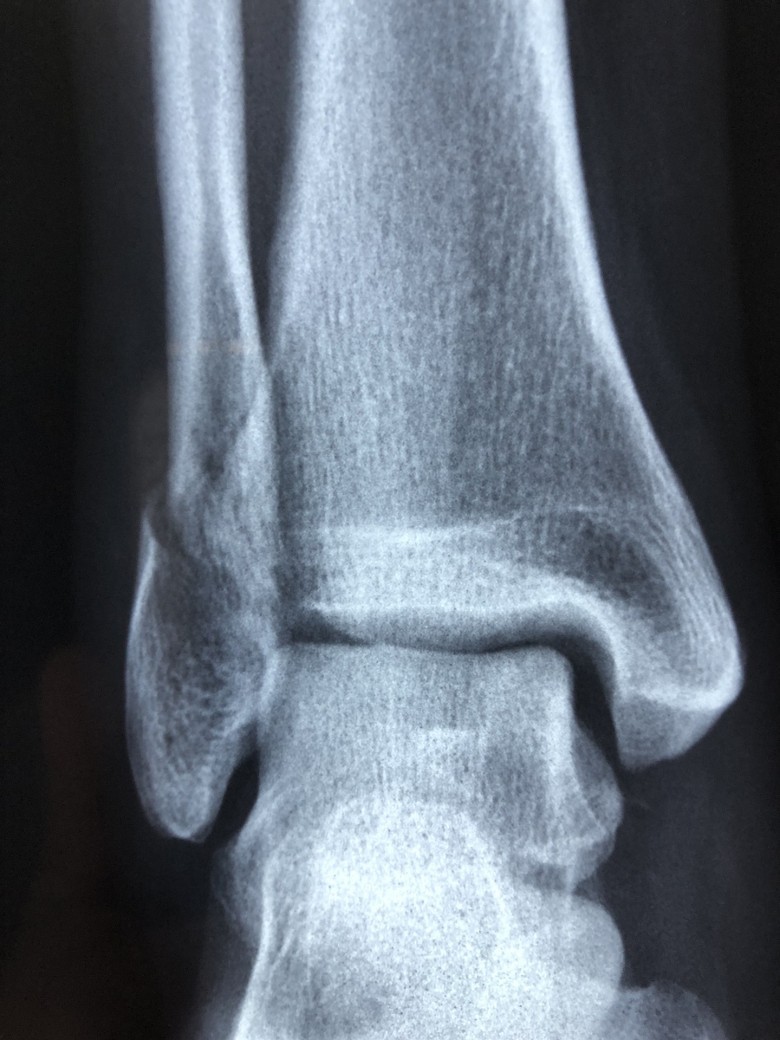

Mechanism of a Sprain

A sprain occurs when there is an injury to the ligaments surrounding a joint. This is usually caused by a twisting or wrenching motion. The basic function of a ligament is to maintain stability and permit mobility or movement. When a ligament gets torn, it loses its otherwise stabilizing ability.